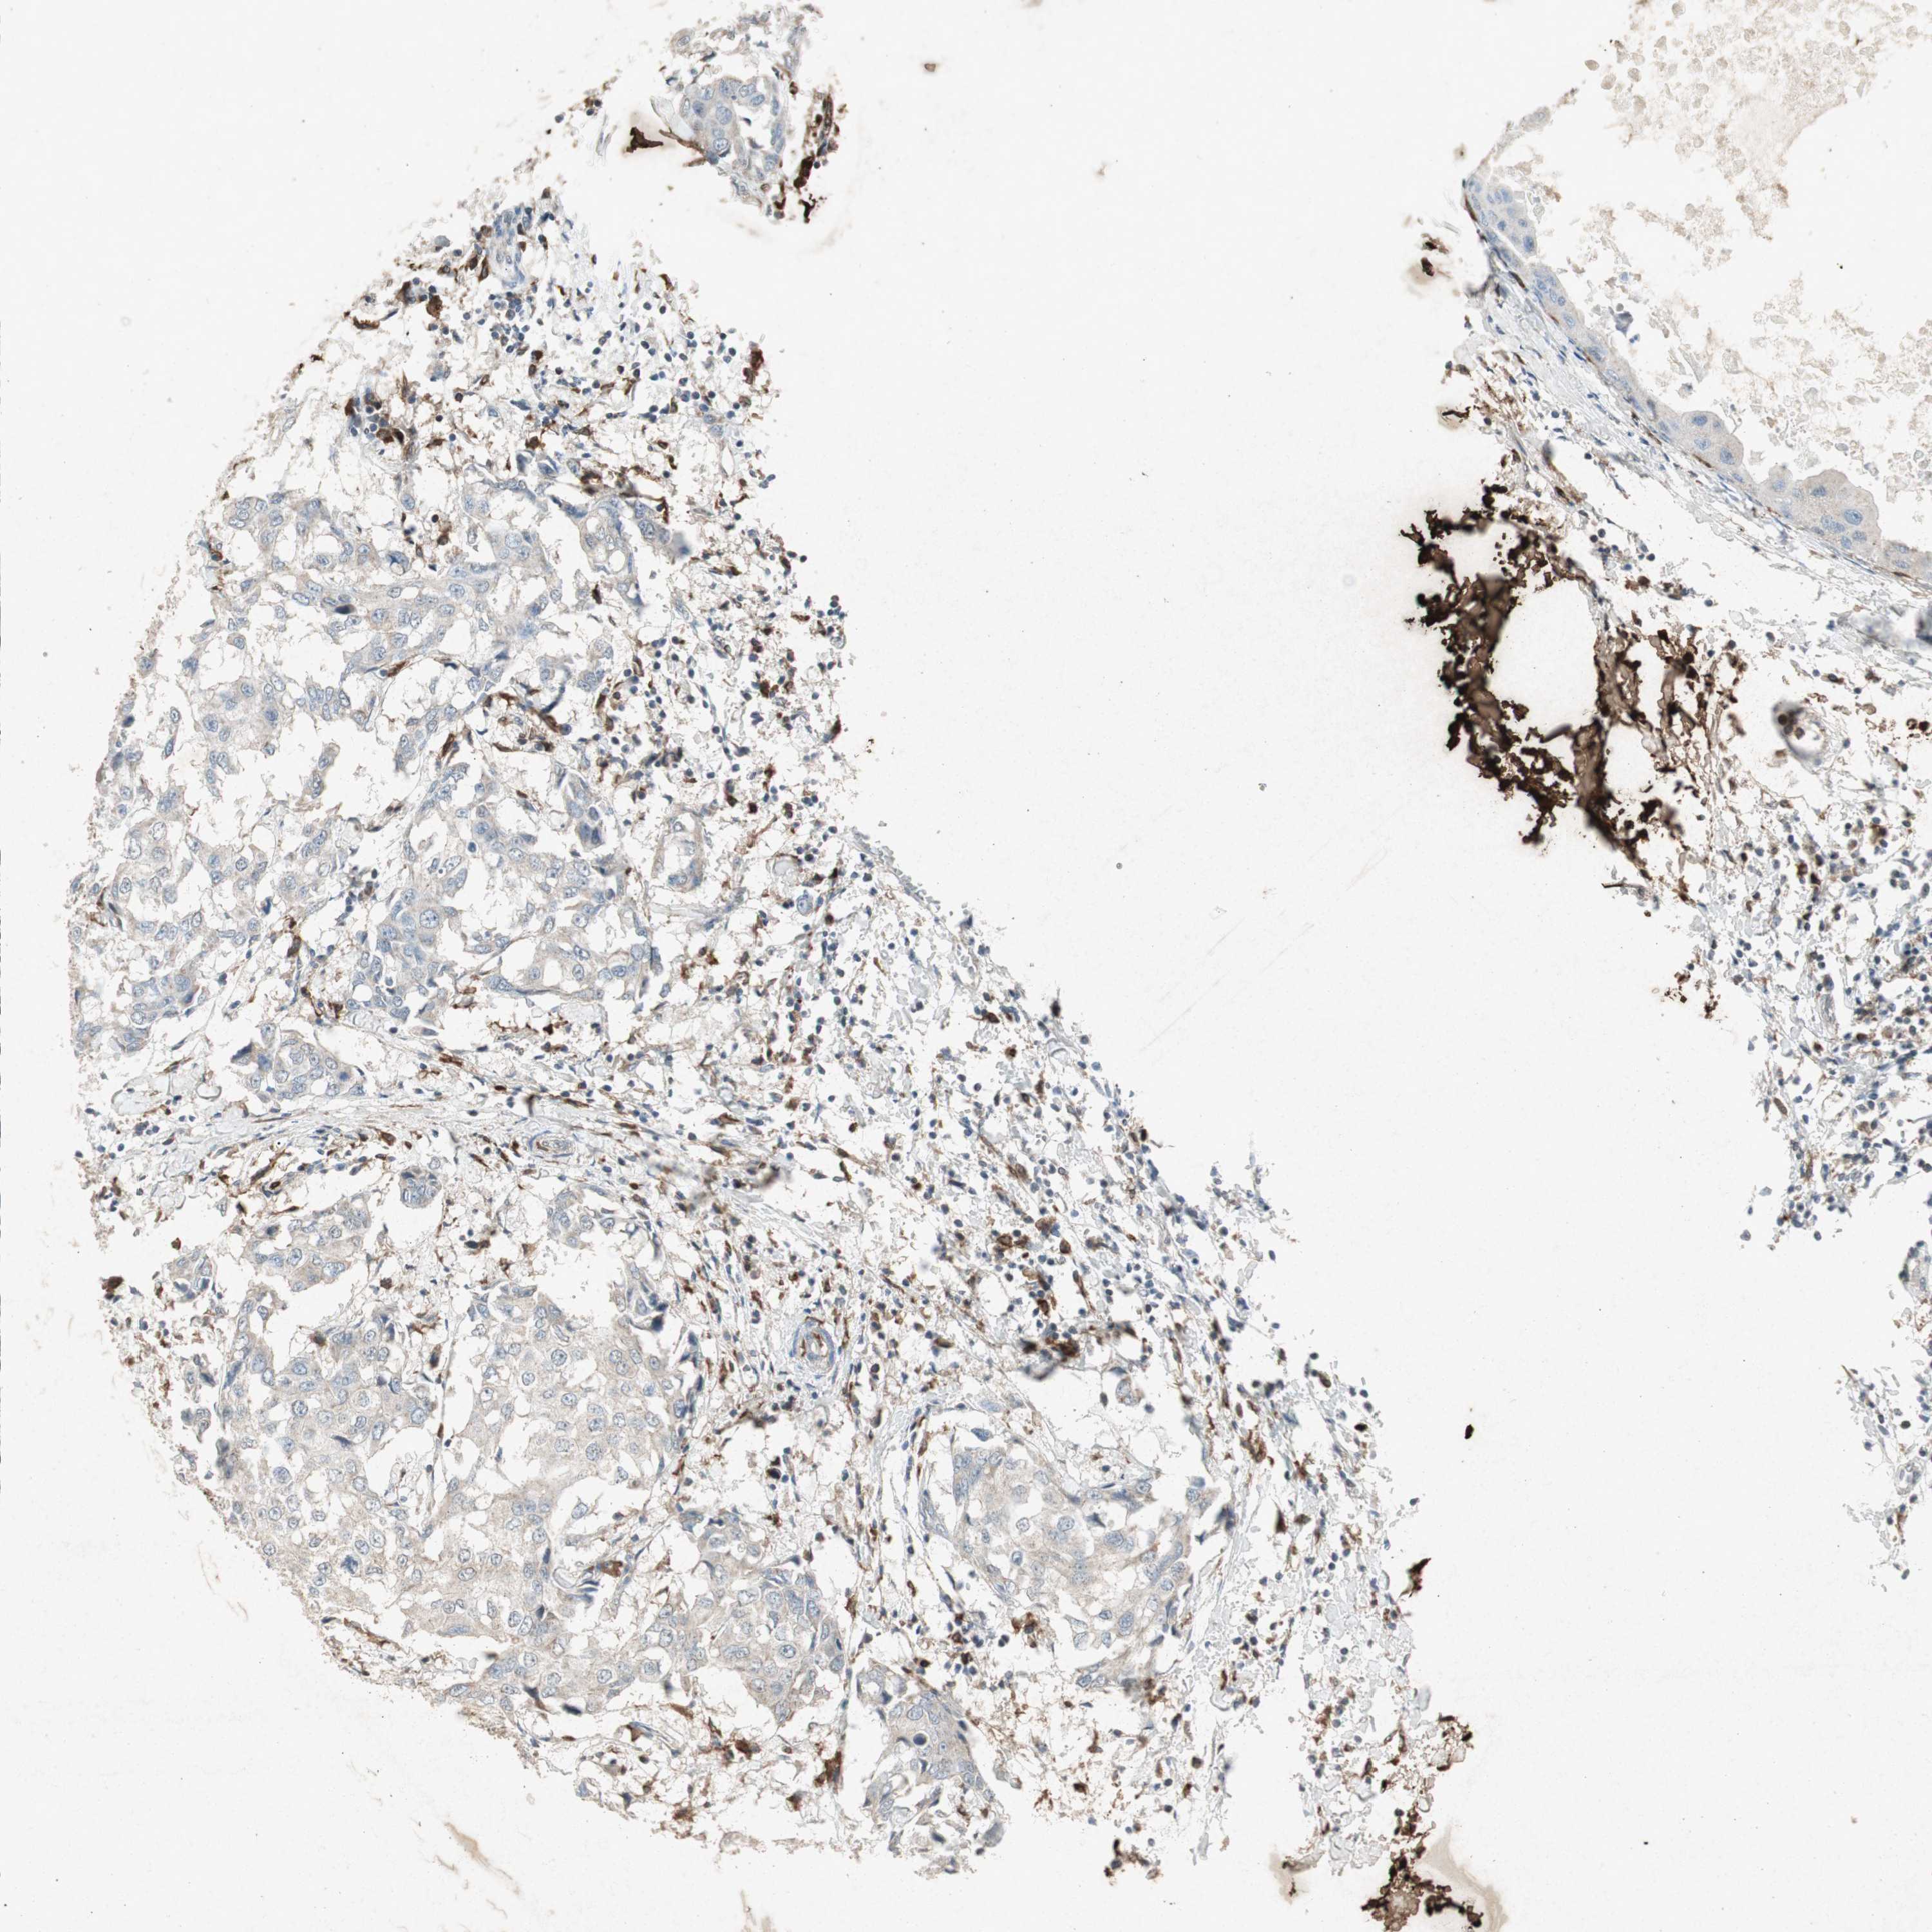

BRCA TCGA BRCA VALIDATION PROTEIN EXPRESSION